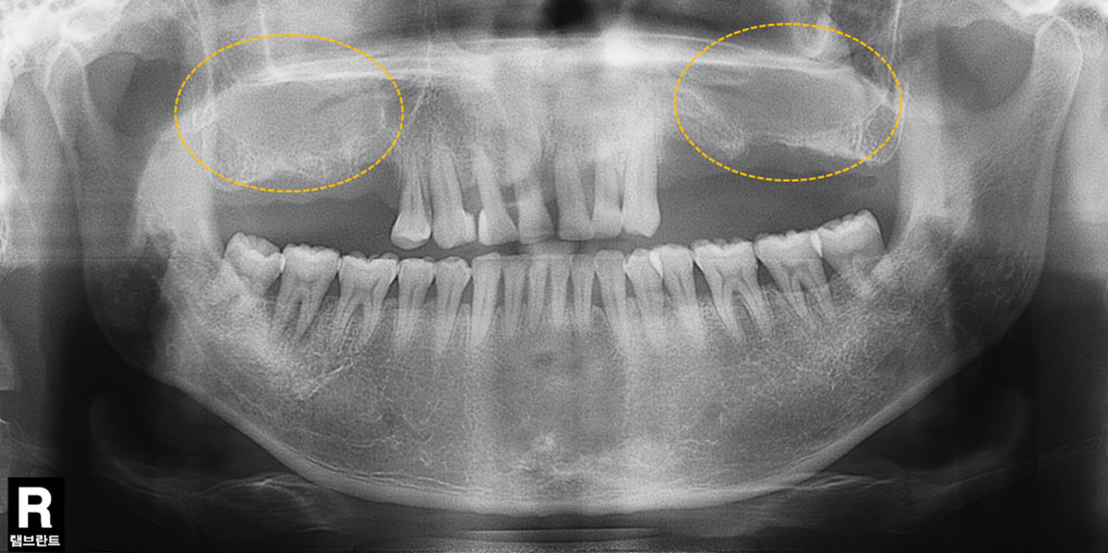

상악동 공간이 내려앉은 경우

치료 후윗턱뼈 공기주머니에 뼈이식

치료 전

치료 후